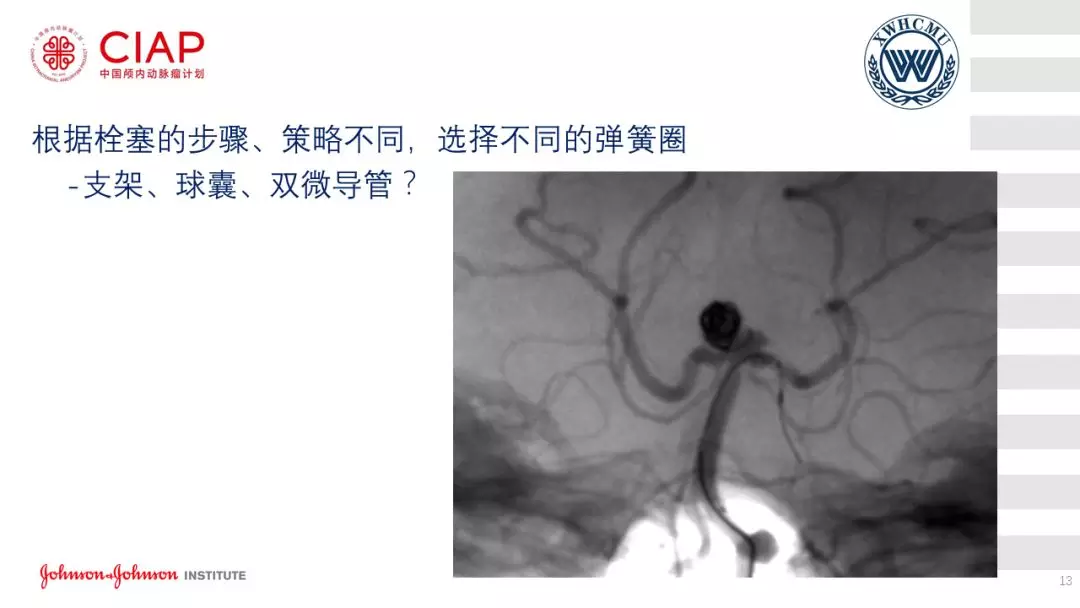

张鹏教授:不同辅助方法下栓塞动脉瘤弹簧圈的选择